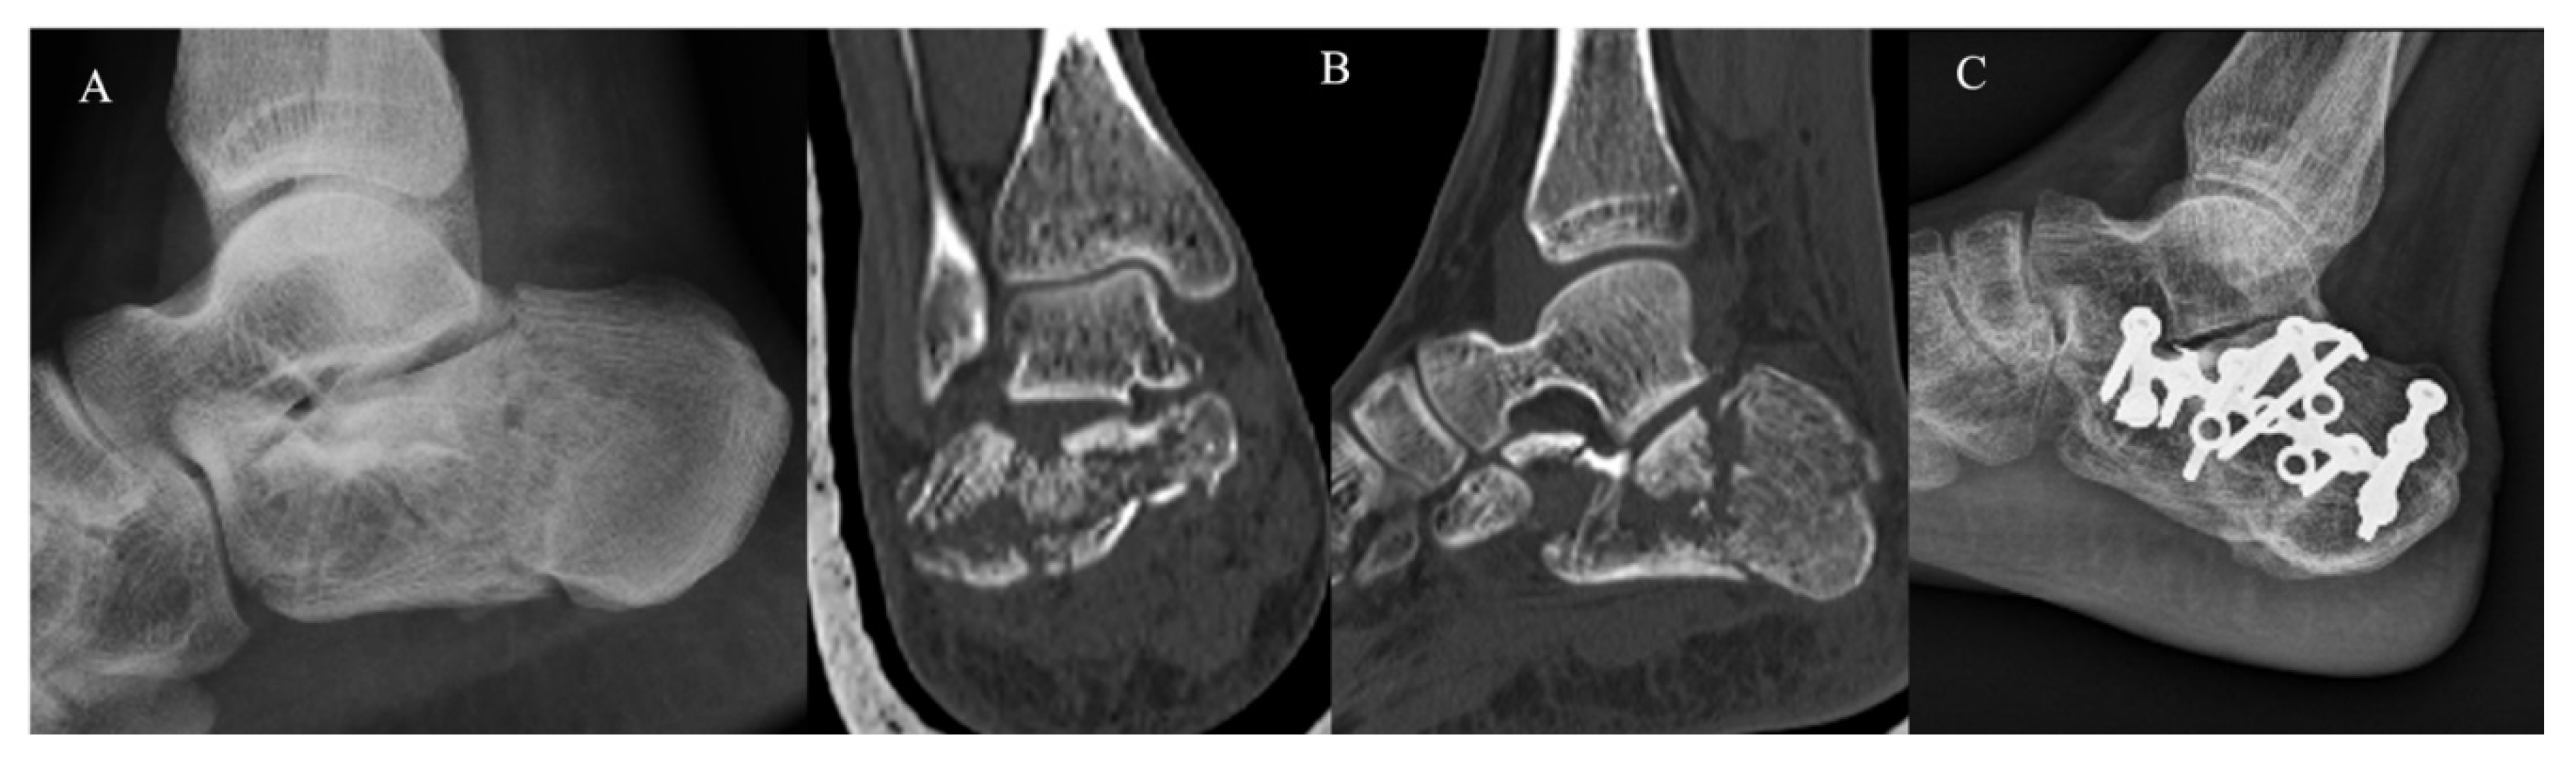

The KG (Figure 2) and PG (Figure 3) consisted of 20 and 22 CF, respectively. The group demographic characteristics and specific mean final follow-up are summarized in Table 1.

Figure 3.

Extended approach and dedicated plate. (A) Pre-operative radiographs; (B) pre-operative CT scan in coronal and sagittal plane showing a Sanders III CF; (C) post-operative radiographs at 4-year follow-up.